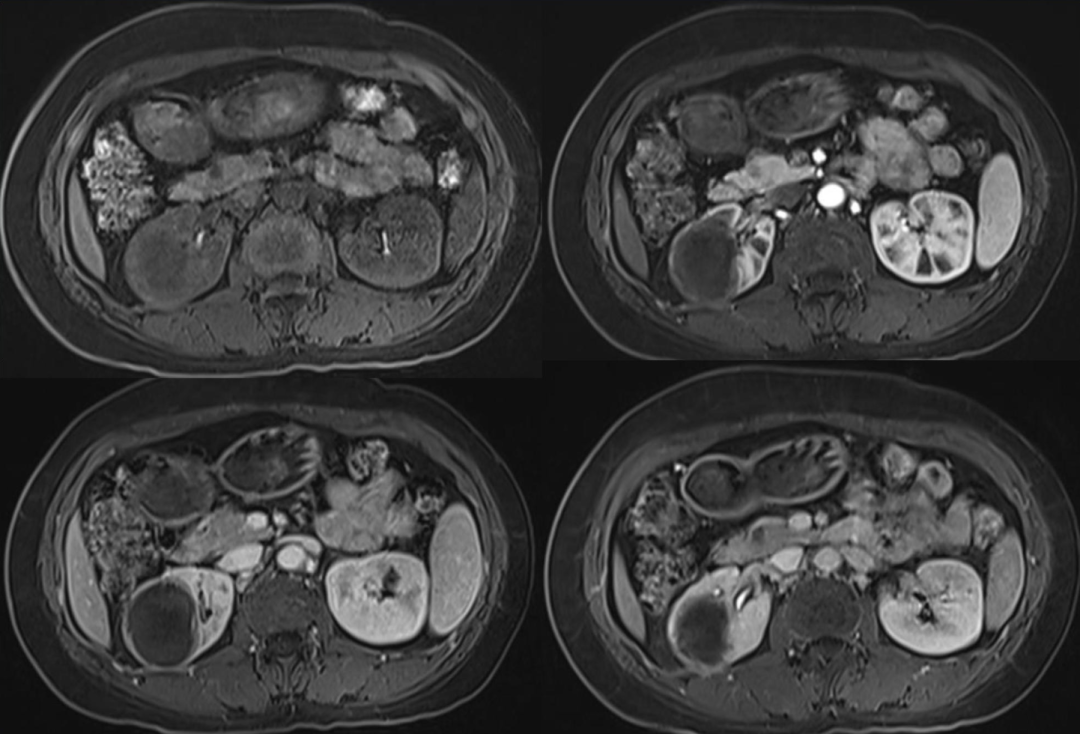

黄色肉芽肿性肾盂肾炎是一种慢性肉芽肿过程,被认为是亚急性/慢性感染导致慢性但不完全免疫反应的结果。最常见的是大肠埃希菌和奇异变形杆菌感染。其特征是肾实质损害、肉芽肿性脓肿及肾间质大量含脂肪的巨噬细胞聚积。含脂肪的巨噬细胞堆积。肾脏最终被大量反应性组织取代,伴有不同程度的肾积水,其环绕鹿角形

"熊掌征"表现为以肾盂肾盏为中心肾实质内多发囊性占位,其中部分囊为结石梗阻所致的肾积水,部分为黄色肉芽肿的脓腔;通常肾盏扩张为主,肾盂扩张常常不显,增强后,病变实性部分均匀强化,坏死区无强化,低密度区边缘环形强化。患肾体积增大或局限性隆起。常常伴有集合系统结石;肾皮质变薄;肾窦脂肪组织减少,多为慢性炎性反应性纤维组织增生所替代;肾周筋膜增厚、肾周间隙渗出积液,严重时可形成脓肿累及腰大肌。腹部X线平片典型的表现是受累的肾脏增大并有鹿角状结石,同侧腰大肌边缘模糊。超声显示肾脏轮廓变形,正常结构消失,中央可探及结石声影。

"熊掌征"主要见于黄色肉芽肿性肾盂肾炎(XGP)。本病在任何年龄均可发病,但以50~70岁多见;女性患者明显多于男性。一般仅有单侧肾脏受累,罕有双侧病变;绝大多数患者肾区疼痛及反复发作的

病例1女性,60岁主诉:反复左